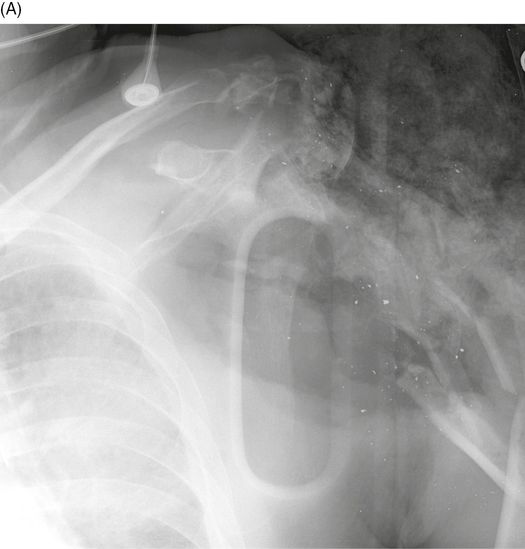

A Anteroposterior shoulder radiograph showing a proximal humeral and How Long Does A Bullet Wound To The Shoulder Take To Heal A gunshot wound is caused when a bullet or other projectile is shot into or through the body. Is it plausible, in a fictional context, to have the protagonist take a bullet and pull through? During this time, the person who was shot is at risk of life threatening complications, such as: To treat a bullet wound, don't move the. How Long Does A Bullet Wound To The Shoulder Take To Heal.